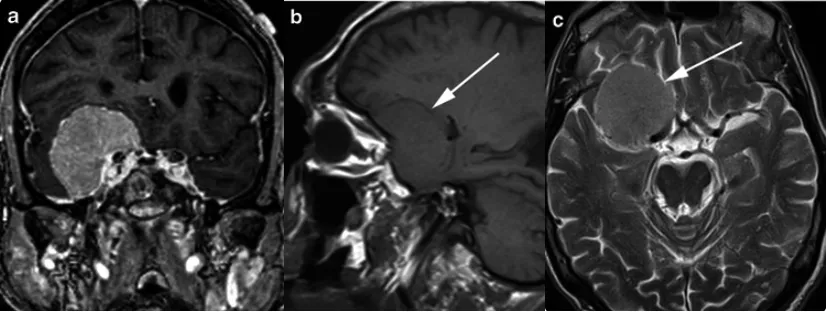

脑膜瘤MRI影像示例分析

案例一:80岁女性患者,精神异常病史1个月。T1加权序列显示右中颅窝底界限清晰、均匀强化的肿块,宽基硬脑膜尾与右侧海绵窦接触。右颞叶受压但未受侵犯。a、b为T2加权像,肿块(箭头指示)呈等灰质信号;c为T1加权像,肿块(箭头指示)呈均匀轻度高信号(与灰质对比)。